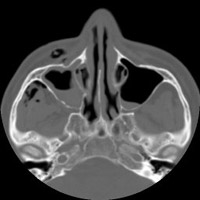

- Click on the image for a larger versionBAxial CT. This image through the maxillary sinuses confirms the presence of subcutaneous gas.